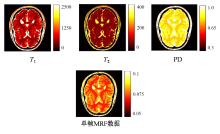

COLLINS D L, ZIJDENBOS A P, KOLLOKIAN V, et al. Design and construction of a realistic digital brain phantom[J]. IEEE Trans Med Imaging, 2002, 17(3): 463-468.

AUBERT-BROCHE B, EVANS A C, COLLINS L. A new improved version of the realistic digital brain phantom[J]. NeuroImage, 2006, 32(1): 138-145.